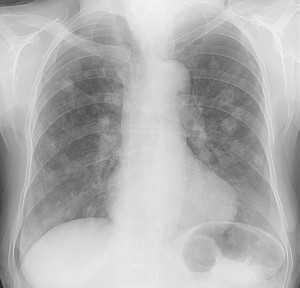

Диагностику заболевания осуществляют врачи-онкологи, к которым больных обычно направляют травматологи и ортопеды. Клинические симптомы при хондросаркоме неспецифичны, поэтому диагноз выставляется на основании дополнительных исследований. При центральных хондросаркомах на рентгеновских снимках обнаруживается очаг деструкции неправильной формы с нечеткими очертаниями, обычно расположенный в метадиафизе. Иногда опухоль выглядит крапчатой из-за мелких очажков обызвествления. Кость вокруг очага вздута.

При периферических хондросаркомах на рентгенограммах выявляется контрастное образование бугристой формы с нечеткими контурами, расположенное на наружной поверхности кости. В переходной зоне между нормальной костью и измененной опухолевой тканью отмечается неравномерное уплотнение. Кортикальный слой кости в этой зоне неровный. Как и при центральной хондросаркоме, может выявляться крапчатость из-за участков обызвествления.

Для уточнения диагноза выполняют трепанобиопсию кости. Забор материала производится из нескольких участков опухоли. В процессе гистологического исследования определяется степень злокачественности хондросаркомы. Как правило, перечисленных исследований достаточно для точной диагностики. В отдельных случаях могут понадобиться дополнительные методы: МРТ кости, компьютерная томография и остеосцинтиграфия. Для выявления метастазов в легких пациентам с хондросаркомой назначается рентгенография грудной клетки.